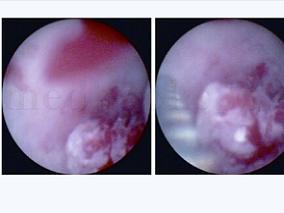

1小时条评论患者男性,47岁。 主诉:间断性全程肉眼血尿3月余。 现病史:患者3个月前无明显诱因发现血尿,呈间歇性反复发作,每次发作时血尿全程、鲜红色,伴尿频、尿急、尿痛,无伴血块,无腰痛、发热、消瘦、潮热、盗汗等症状。曾在多家医院多次诊治,但未查明血尿原因。经...